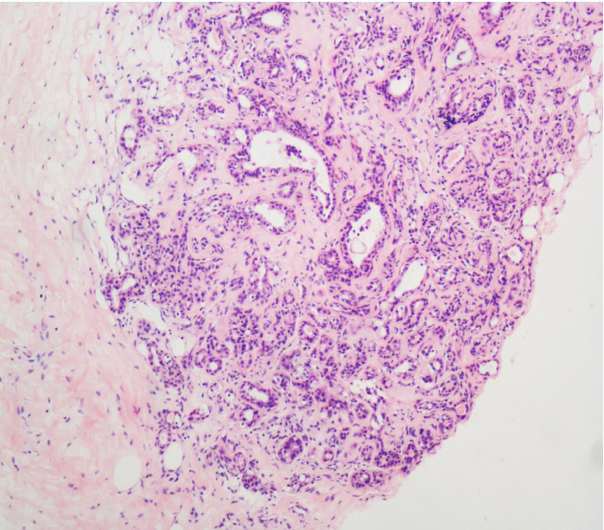

(1)浸润性导管癌 (invasive ductal carcinoma)

由导管内癌发展而来,癌细胞突破导管基底膜向间质浸润,是最常见的乳腺癌类型,约占乳腺癌70%左右。

镜下,组织学形态多种多样,癌细胞排列成巢状、团索状,或伴有少量腺样结构。可保留部分原有的导管内原位癌结构,或完全缺如。癌细胞大小形态各异,一般多形性明显,核分裂像多见,常见局部肿瘤细胞坏死。癌细胞周围间质有致密的纤维组织增生,癌细胞在纤维间质内浸润生长,二者比例各不相同。

以往根据癌实质和纤维组织间质的不同比例分为单纯癌(carcinoma simplex) (癌实质与间质比例大致相等)、硬癌(scirrhous carcinoma)(间质成分占优势,少量癌细胞呈条索状分布于增生的纤维组织中)和不典型髓样癌(癌实质多于间质),现统称为浸润性导管癌。

肉眼观, 肿瘤呈灰白色,质硬,切面有沙砾感,无包膜,与周围组织分界不清,活动度差。常可见癌组织呈树根状侵入临近组织内,大者可深达筋膜。如癌肿侵及乳头又伴有大量纤维组织增生时,由于癌周增生的纤维组织收缩,可导致乳头下陷。如癌组织阻塞真皮内淋巴管,可致皮肤水肿,而毛囊汗腺处皮肤相对下陷,呈橘皮样外观。晚期乳腺癌形成巨大肿块,在癌周浸润蔓延,形成多个卫星结节。如癌组织穿破皮肤,可形成溃疡。